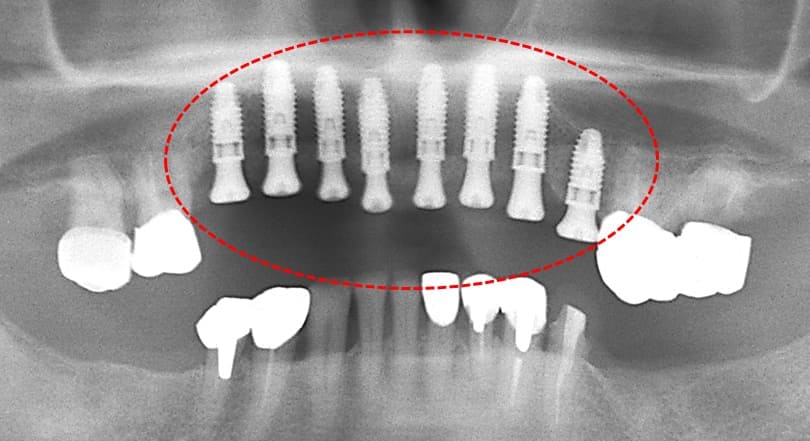

初診時のパノラマXP所見

上顎前歯を含む第2小臼歯から対側の第2小臼歯までの10本のブリッジが脱離しそれを支えていた歯自体が保存できない状態であった。また下顎の臼歯部も欠損しており、このことで垂直的な咬合の安定が得られず前歯に負担がかかる崩壊脱離したと考えられる。

#15,14,21,22,23,27,36が残根状態で温存は不可能であり、患者さん自身もそれを自覚しておられた。

上顎前歯部と小臼歯部の温存不可能な残根を抜歯して1か月ほど待機して歯肉が抜歯窩を完全に閉鎖した状態でCTと口腔内の印象を取り最終補綴の予想WAX UPを1行いサージカルガイドを作成した。その後、上顎にインプラント8本を埋入した。

上顎にインプラント8本を埋入した術後のパノラマXP所見:上顎骨に対するインプラントの長さに関しては12mm-10mmが適切であり前歯部では12mmを小臼歯部では10mmを選択している。また左下のブリッジに関しては温存できなかった第2大臼歯が抜去されている。